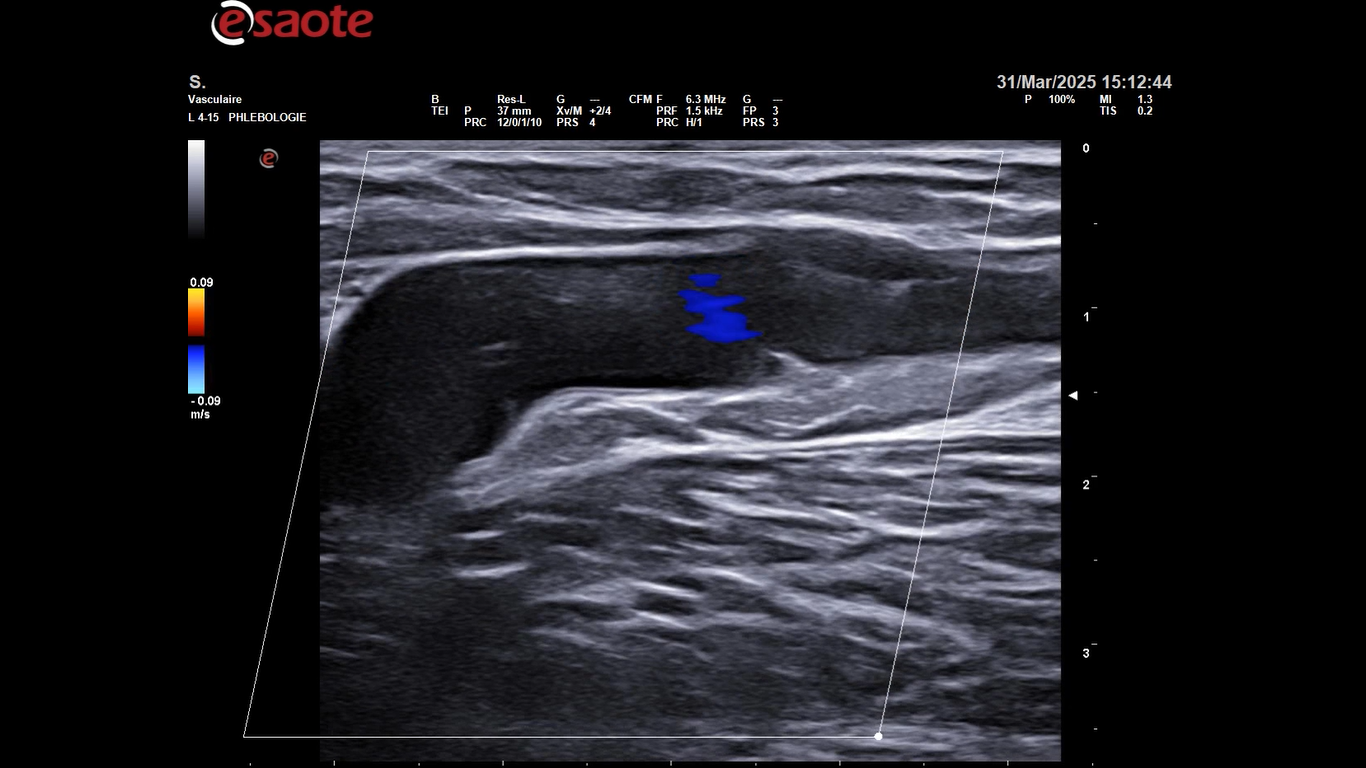

L’EIS est une école privée qui accueille les médecins vasculaires de tous les pays qui souhaitent optimiser la prise en charge de leurs patients et leur proposer une méthode de soin non invasive, efficace et sûre pour le traitement des varices : la sclérothérapie échoguidée à la mousse.

L’EIS accueille des médecins qui ont déjà acquis les bases théoriques de la médecine vasculaire et qui souhaitent apprendre à pratiquer l’échoDoppler veineux et la sclérothérapie ou à améliorer leur savoir-faire.

L’EIS vous propose une formation d’une journée, le vendredi 28 novembre 2025, directeur du cours : Dr Mario Sica, cette session vous permettra d’optimiser la prise en charge diagnostique et thérapeutique de vos patients grâce à une approche avancée de la sclérothérapie échoguidée en 3D.